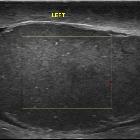

testicular infarction

Ultrasound

image of patient presenting with right testis pain in past 24 hours. Hypoechoic and avascular upper segment of R testis. Segmental testicular infarction.